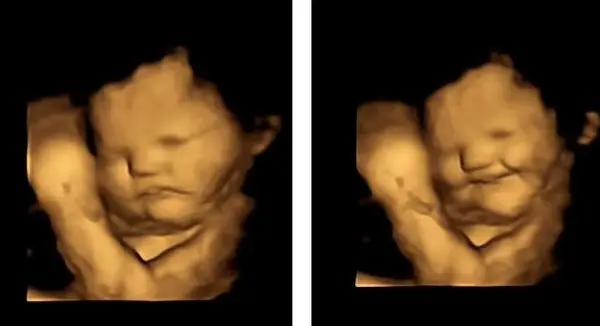

نتایج این پژوهش نشان داد که جنین‌ها بلافاصله پس از خوردن هویج توسط مادرشان، لبخند می‌زنند اما وقتی مادرها کلم‌برگ را خوردند، واکنشی حاکی از انزجار نشان دادند.

هنگامی که زنان هویج مصرف کردند، جنین‌ها در اسکن لبخند زده بودند اما زمانی که آنها کپسول کلم‌برگ را مصرف کردند، جنین‌ها انزجار را در چهره خود نشان دادند.